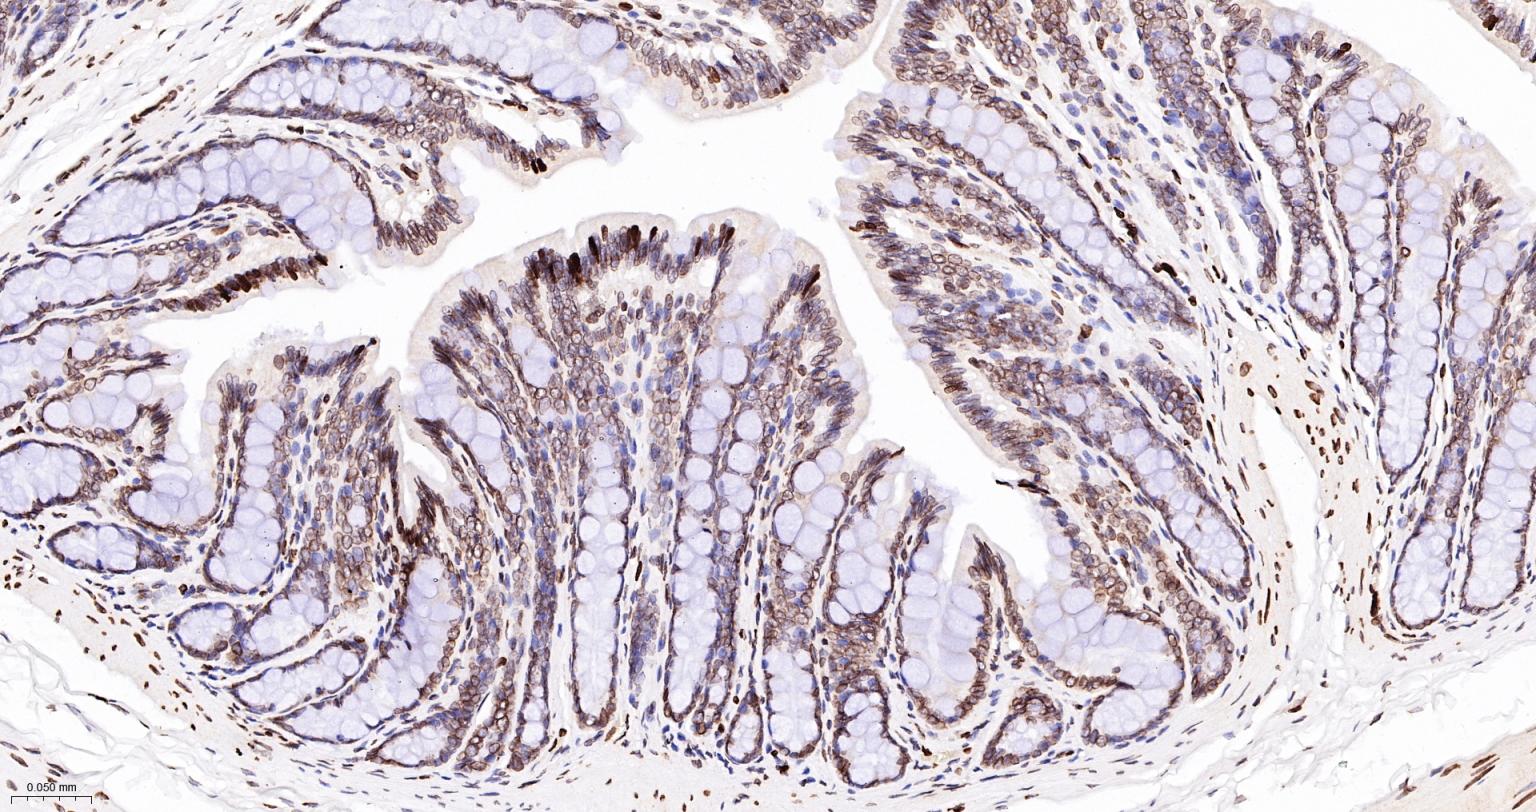

Paraformaldehyde-fixed, paraffin embedded Rat Colon; Antigen retrieval by boiling in sodium citrate buffer (pH6.0) for 15 min; The section was incubated with Lamin A/C Monoclonal Antibody, Unconjugated (bsm-51683M) at 1:100 overnight at 4°C, followed by conjugation to the bs-40296G-HRP and DAB (C-0010) staining.